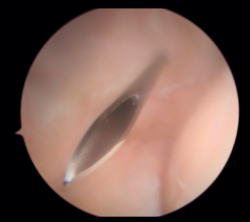

En primer lugar, se realiza el portal anteromedial de visión, incidiendo únicamente la piel y realizando disección roma con un mosquito recto. A continuación, se introduce la vaina del artroscopio, atravesando de forma anterior y proximal el septo fibromuscular medial, en dirección a la cabeza del radio, de forma posterior y distal, para evitar lesionar el nervio cubital y el paquete vascular anterior del codo. Una vez introducida la óptica en el portal medial, se procede a realizar el portal lateral proximal como portal de trabajo. Se realiza bajo visión directa, utilizando como guía una aguja intramuscular de fuera a dentro, para localizar el punto de entrada que permita mejor ángulo de trabajo (Figura 4). Posteriormente, se incide en la piel y se realiza disección roma con un mosquito recto para entrar en la articulación (Figura 5).

Figura 5. Realización del portal lateral (paciente en decúbito lateral, codo derecho, visión desde el portal medial).